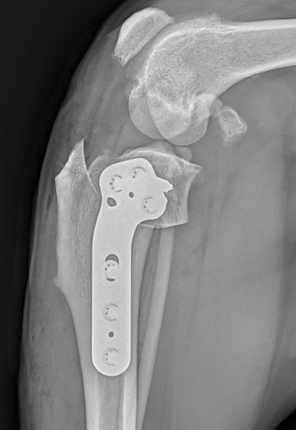

Then, the bone is cut with a special saw, and the tibial plateau segment is rotated into the desired position. The cut in the bone is stabilized with a bone plate and screws.